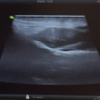

A 40 years old man from north India, working as a farmer in sugarcane fields, presented to our department with insidious onset, gradually progressive painless firm swelling of right foot of 5 years duration. It was associated with multiple sinuses with scanty discharge and extrusion of black grains (Fig. 6, 7). No associated systemic features were present. The patient was initially treated in his local town by different physicians for the past 3 years. However, the disease persisted. Patient was diagnosed here based on clinical features as Madura foot. X-ray showed nonspecific osteomyelitic changes of tarsal bones (Fig. 8). MRI picture showed the characteristic multiple sinuses with ‘dot in circle’ picture (Fig. 9). Further histopathological confirmed fungal mycetoma. The patient was then started on itraconazole 400 mg in two divided doses for 12 months. At 3 months, patient became symptomatically better with marked decreased in discharge. At 6 months, he had complete resolution of discharging sinuses and the skin returned to normal. He completed his medical therapy at 12 months.

X-ray features are typical of soft tissue swelling, cortical erosions and thickening, periosteal reaction, bony lucencies, joint destruction, osteopenia, and sometimes “moth eaten appearance” with bone lysis are seen. MRI can clinch early diagnosis of the condition. The highly specific “dot in circle” sign is characteristic of early soft tissue infection [9]. Newer techniques of diagnosis like DNA sequencing guide in identifying the causative organism. A case report was published where Madura foot negative on culture was finally diagnosed with amplification and sequence analysis of fungal ribosomal DNA segments [10].